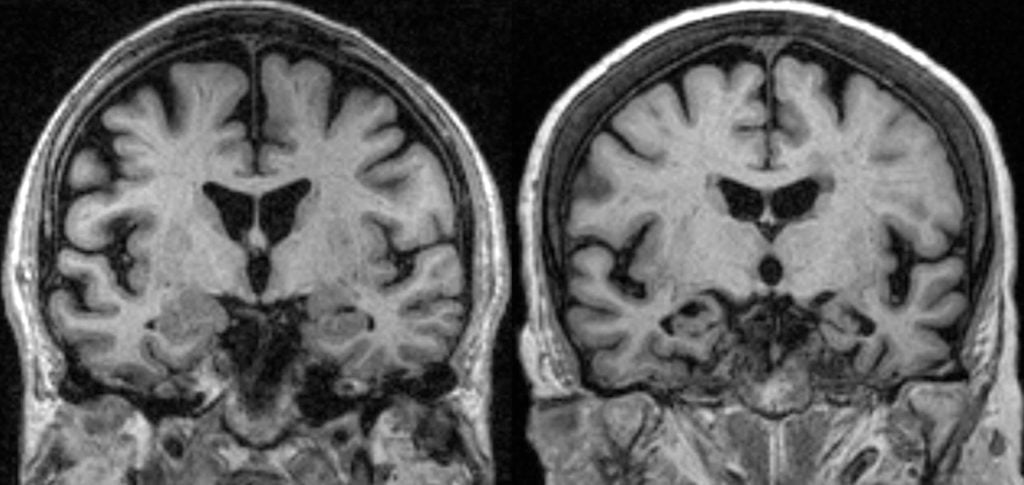

This is a rare condition which can cause gradually worsening problems with the memory, speech, movement and swallowing. The corticobasal degeneration is often called corticobasal syndrome. The corticobasal degeneration is caused by increasing numbers of brain cells becoming damaged or dying over time. The most cases of the corticobasal degeneration develop in adults who are aged between 50 and 70 [1]. It is known fact that the symptoms of corticobasal degeneration gradually worse over time. They can vary and many people can have just a few of them.